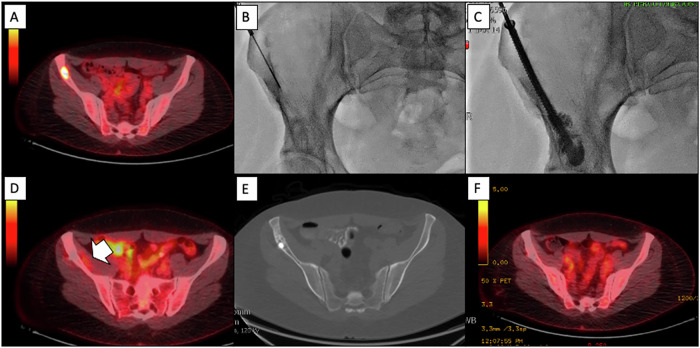

Materials and methods: We reviewed 43 patients (23 males, 20 females) with 51 lesions (44 metastatic, 7 benign) treated with MWA from January 2016 to December 2023. Pain intensity was measured using the Visual Analogue Scale (VAS), SF-36 Bodily Pain Scale, and Patient Global Impression of Change (PGIC) from pre-operation to various follow-up stages. Adverse events were categorized according to the Society of Interventional Radiology (SIR) grading system.

Results: The procedure demonstrated 100% technical success. Grades I and III adverse events were observed in 8.3% (3/36) and 2.8% (1/36) of patients with metastatic disease, respectively. In those with benign lesions, no adverse events were reported. A significant reduction in pain was observed, with the VAS score decreasing by 74.3% from baseline to the last follow-up [6.7 ± 2.3 (range: 0-10) to 1.8 ± 2.3 (range: 0-7) (p < 0.001)] for metastatic patients, and from 5.7 ± 2.1 (range: 3-8) to 0 ± 0 (range: 0-0) by the final follow-up (p = 0.0011) for benign lesions. 77.8% (29/36) of metastatic patients, and all (7/7) benign patients were much or very much improved according to Patient Global Impression Change. Complete imaging response was achieved in 55.6% (20/36) of metastatic lesions. At last follow-up, 25% (9/36) had radiological evidence of recurrence, with a median recurrence time of 13 months (IQR: 8-14). Complete response was achieved in all benign lesions.